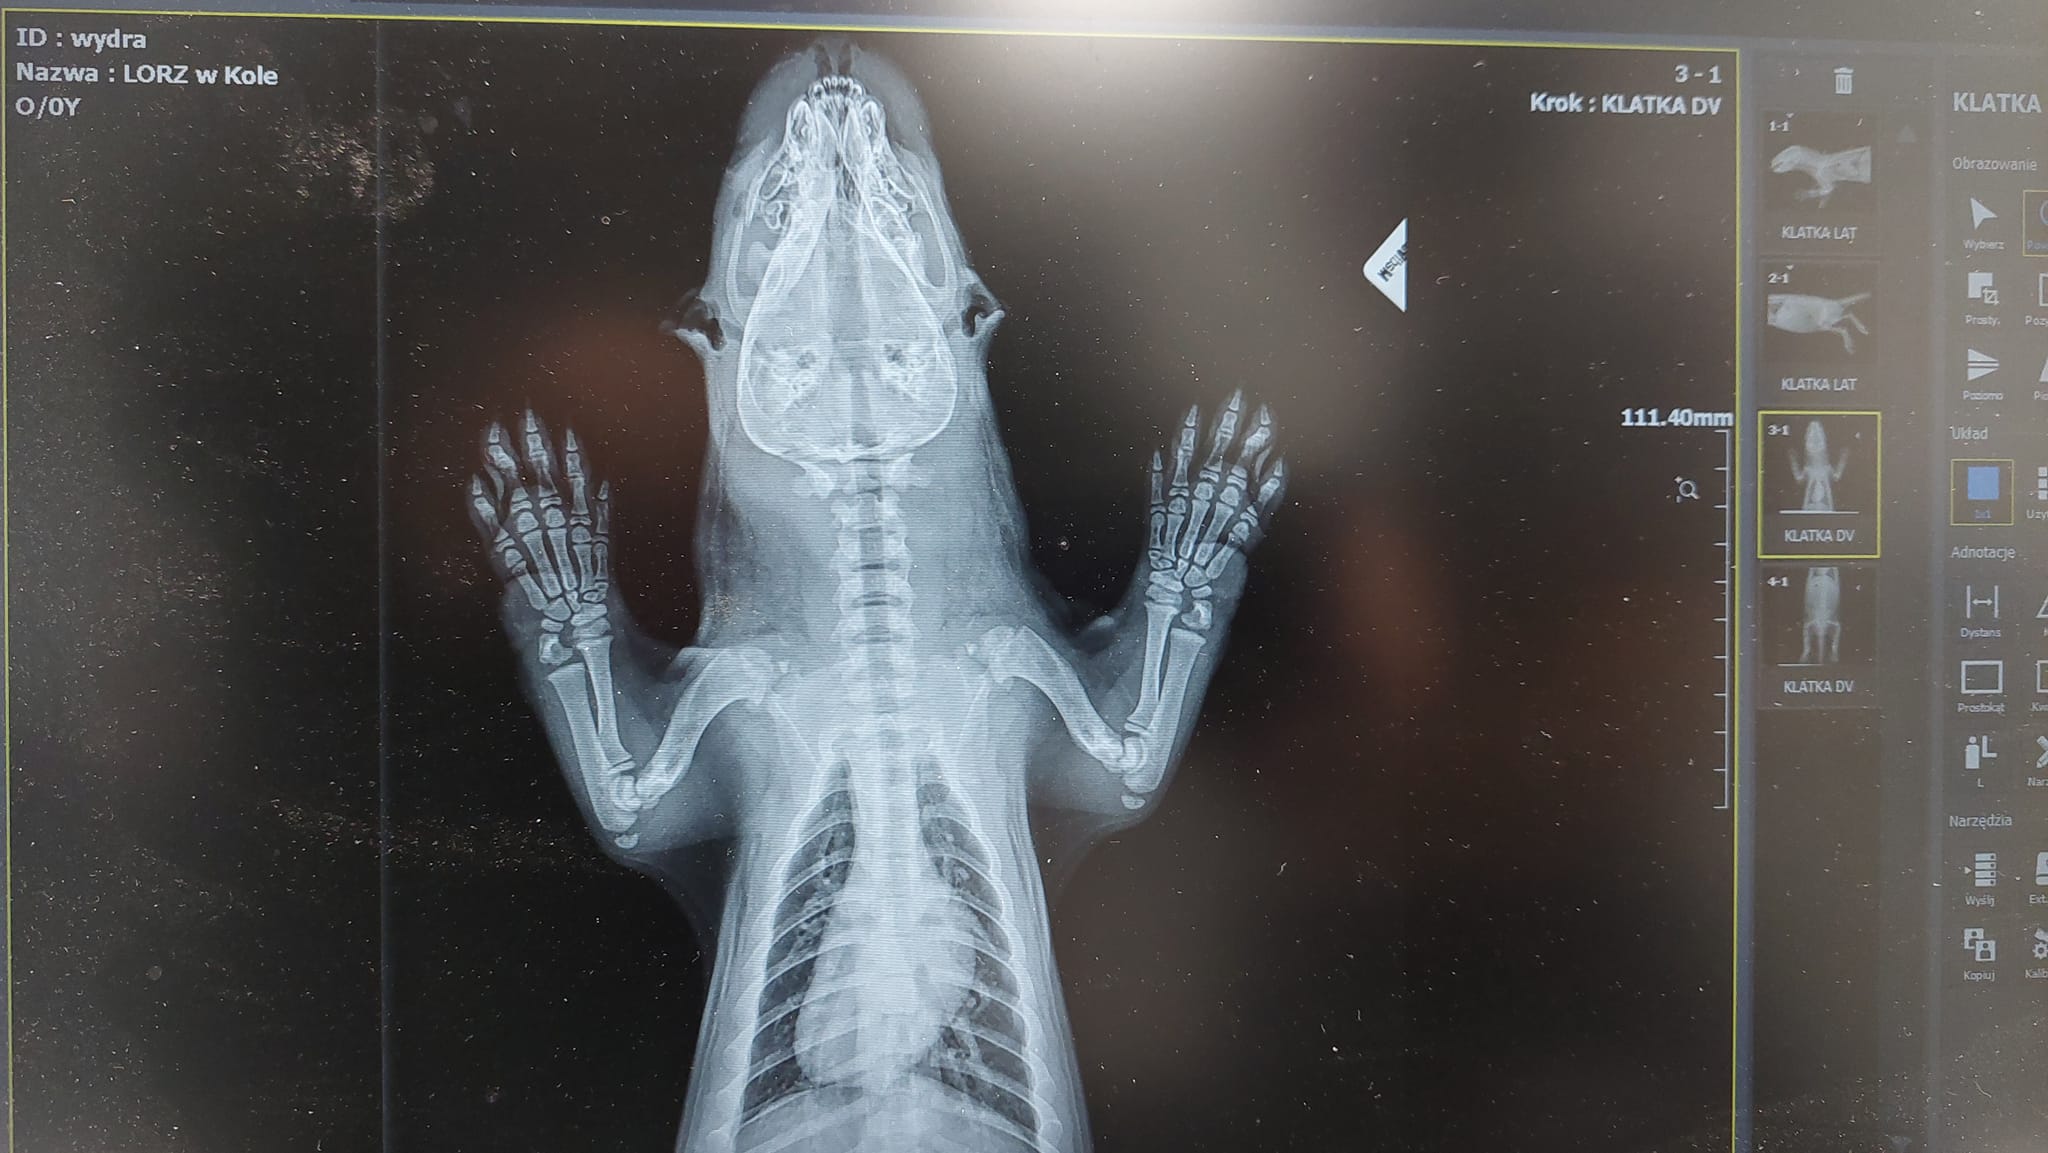

– Młoda wydra poturbowana przez psa. Uważajmy na spacerach z naszymi czworonożnymi pupilami. Na szczęście brak złamań, ale zwierzę miało obfity krwotok z nosa. Jest to tegoroczne szczenię Wydry Europejskiej (Lutra lutra) z rodziny łasicowate – głosił pierwszy komunikat specjalistów z Leśna Osada Edukacyjna w Kole – Leśny Ośrodek Rehabilitacji Zwierząt.